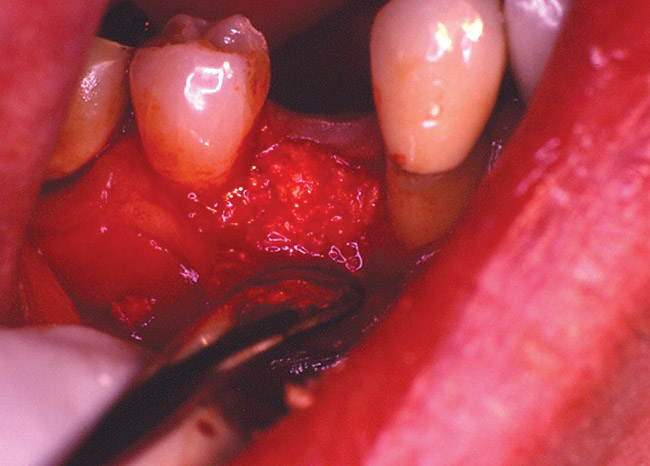

The patient was a 50-year-old woman who needed to have tooth No. 3 removed, as it was deemed unrestorable. No socket preservation was planned before the extraction of the tooth. The tooth was extracted using forceps and elevators (Figure 1A). At the time of the extraction, it was noted that a portion of the buccal plate of bone was also removed. After a period of healing, a significant concavity was present, due to buccal loss of bone (Figure 1B and Figure 1C). The treatment in such a case usually requires additional grafting to compensate for a lack of bucco-lingual width before completing implant-supported restorations.

Figure 1a  Tooth No. 3 was extracted. At the time of extraction, it was noted that a portion of the buccal alveolar plate was attached to the roots of the tooth.

Figure 2b  After extraction of the tooth, the socket was curetted. It was noted that there was bone loss on the buccal aspect because of the presence of infected tissue.

Figure 2c  The socket was grafted using a combination of freeze-dried bone allograft and a calcium sulfate bone graft barrier.